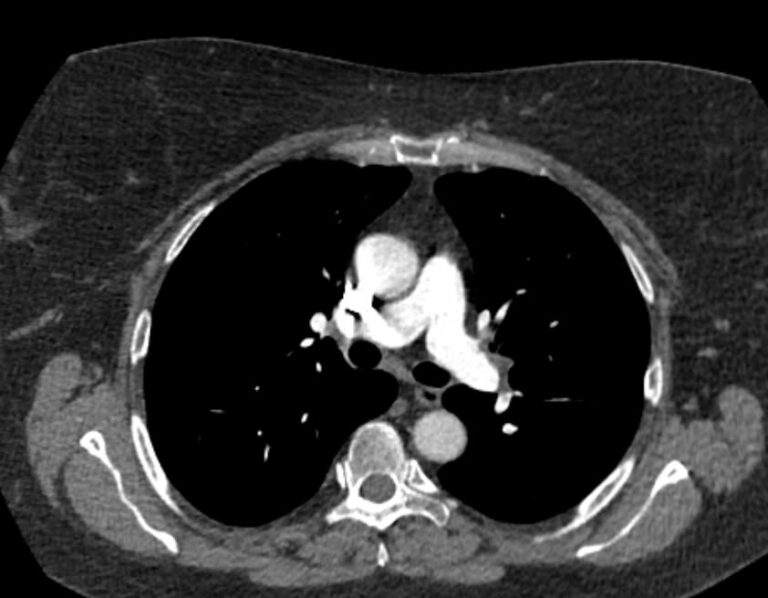

Наиболее информативным, при этом быстрым и неинвазивным (то есть без вмешательства в организм пациента), методом диагностики патологии легочной артерии является мультиспиральная компьютерная томография (КТ-ангиография). Методика основана на использовании рентгеновского излучения в сочетании с цифровой обработкой данных для получения трехмерных изображений сосудистой системы.

Для визуализации кровеносных сосудов в обязательном порядке применяется контрастное усиление. Для этого в вену пациента вводится йодсодержащий контрастный препарат, который попадая в кровоток активно поглощает рентгеновские лучи и ярко контрастирует сосудистую систему, в том числе легочной артерии, на фоне окружающих тканей. Использование контраста дает возможность визуализировать даже мелкие артерии и выявить патологию.

В наших диагностических центрах КТ-ангиография легочной артерии проводится на современных мультиспиральных компьютерных томографах экспертного уровня TOSHIBA AQUILION. Оснащение аппаратов позволяет получать детальные снимки и трехмерные изображения сосудистой системы легочной артерии, при этом применение скоростной мультисрезовой методики сканирования значительно снижает уровень лучевой нагрузки на пациента.